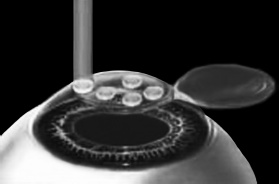

ЛАСИК – основной метод лазерной коррекции в мире в настоящее время. По большому счету, ФРК и ЛАСИК – единственные методы коррекции. Остальные методы являются либо модификациями ФРК и ЛАСИК, либо «компромиссом» между ними. Эпителий роговицы не трогают, так как он – залог быстрого заживления. Накладывают на глаз вакуумное кольцо – стальную присоску кольцевидной формы с присоединенной к нему трубочкой. Через трубочку из присоски отсасывается воздух, чтобы создать относительный вакуум. Отсасывает воздух главный аппарат для проведения ЛАСИКа – микрокератом. Это прибор размером с коробку из-под обуви. Его предназначение – срезание поверхностной крышки роговицы. К глазу присоединяют вакуумное кольцо, окружающее роговицу. Глаз четко фиксируется относительно кольца и сдвинуться с места может только с кольцом, в отверстие которого выступает купол роговицы. Затем к кольцу присоединяется головка микрокератома. Это второй инструмент микрокератома и соединяется с ним или шнуром, или тонким шлангом. Головка крепится на турбине, и вместе они имеют вид толстой шариковой ручки с обрубленным концом. Эту «ручку» хирург держит в правой руке, а вакуумное кольцо – в левой. Эта «ручка» нужна, чтобы сформировать крышечку роговицы. Внутри головки есть очень острое одноразовое лезвие. Турбина, соединенная с головкой, может двигать одноразовое лезвие туда-сюда, пилящими движениями. Можно резать роговицу, как хлеб, – пилящими движениями. И тут самое главное – скорость. Одноразовое лезвие делает 15000 пилящих движений в минуту. При такой скорости назвать это срезанием роговицы уже трудно, скорее это отслаивание верхних слоев. ![]() Рис. 3. Схема формирования роговичного лоскута с помощью микрокератома. Иллюстрация с сайта Международного лазерного центра www.optics.ru Итак, головка присоединяется к вакуумному кольцу и по специальным полозьям двигается над куполом роговицы (рис. 3). Срез, или отслаивание (называйте, как хотите), проводится не полностью, у крышечки (роговичного лоскута) остается маленький участок на периферии, соединяющий ее с роговицей (рис. 4). ![]() Рис. 4. Роговичный лоскут сформирован. Иллюстрация с сайта Международного лазерного центра www.optics.ru После формирования роговичного лоскута убирают инструменты микрокератома, затем шпателем откидывают его вбок (рис. 5). Обнажается роговичное ложе, то есть место, на котором лежал лоскут. Это верхние слои стромы роговицы. Ложе осушают тупфером и так же, как и при ФРК, настраивают лазер и испаряют несколько микрон вещества стромы (рис. 6). Потом промывают строму водой и шпателем укладывают лоскут на место. ![]() Рис. 5. Роговичный лоскут откинут в сторону. Иллюстрация с сайта Международного лазерного центра www.optics.ru ![]() Рис. 6. Луч эксимерного лазера испаряет на роговичном ложе несколько микрон стромы роговицы. Иллюстрация с сайта Международного лазерного центра www.optics.ru Стоит один раз моргнуть и лоскут скомкается и зрения не будет. Его бы пришить на место. Но швы деформируют роговицу. Все проще. Лоскут разглаживают мокрым тупфером, прижимая его ровненько к старому месту (рис. 7 и 8). Только место не старое, с роговичного ложа удалили несколько микрон в виде причудливой ямки (при коррекции близорукости). ![]() Рис. 7. При коррекции близорукости на роговичном ложе формируется «ямка». Иллюстрация с сайта Международного лазерного центра www.optics.ru ![]() Рис. 8. Роговичный лоскут укладывается на место. Иллюстрация с сайта Международного лазерного центра www.optics.ru Края роговичного лоскута осушают сухим тупфером. Влага, оставшаяся под лоскутом в ямке роговичного ложа, высасывается в тупфер. Лоскут притягивает к ложу, как вакуумную присоску. Вакуумом начали, вакуумом закончили. Ждем, когда закончится приживление лоскута к ложу. Эпителий цел и невредим. А значит, никаких болей. Около трех часов возможны слезотечение и светобоязнь. И все (рис. 9). ![]() Рис. 9. Форма роговицы до проведения коррекции (а) и после коррекции близорукости (б). Испарение нескольких микрон толщины роговицы привело к уменьшению ее кривизны в центре. Иллюстрация с сайта Международного лазерного центра www.optics.ru Хирурги о ЛАСИКе говорят: «90 % хирургии и 10 % долечивания». Лазерный субэпителиальный кератомилез (LASEK) Модификация ФРК. Чтобы укоротить неприятный послеоперационный период, эпителий, обработанный спиртовым или солевым раствором, отслаивают очень бережно, с помощью специальных инструментов, в виде цельного лоскута. А после испарения эксимерным лазером боуменовой мембраны и нужного количества слоев стромы этот эпителиальный лоскут укладывают обратно и, чтобы он не сместился, прижимают мягкой контактной линзой. Через 3–4 дня эпителий заживает, а благодаря линзе и даже еще не приживленному эпителиальному лоскуту боль и светобоязнь не беспокоят пациента с первых часов после коррекции, а зрение восстанавливается на пару недель быстрее, чем при ФРК. Также одной из модификаций ФРК является MAGEK. Основным отличием от ФРК является применение препарата Митомицин С (Mitomycin-С), который блокирует «слишком быстрое деление клеток» и снижает риск возникновения хейза. Эпи-ЛАСИК (Epi-LASIK) Нечто среднее между ЛАСИК и LASEK. Для отделения эпителия используются не спиртовой или солевой растворы, а специальный аппарат, очень похожий на микрокератом. Аппарат называется эпикератомом. Он отслаивает эпителий вместе с частью боуменовой мембраны в виде лоскута, похожего на лоскут при ЛАСИКе, только гораздо тоньше. После проведения коррекции лоскут также прижимают контактной линзой. Но не поврежденный химическим ожогом эпителиальный лоскут, да еще с остатками боуменовой мембраны, значительно сокращает период заживления и восстановления и снижает другие недостатки ФРК и LASEK, о которых будет сказано ниже. Рефракционный эксимерлазерный интростромальный кератомилез (РЭИК) |